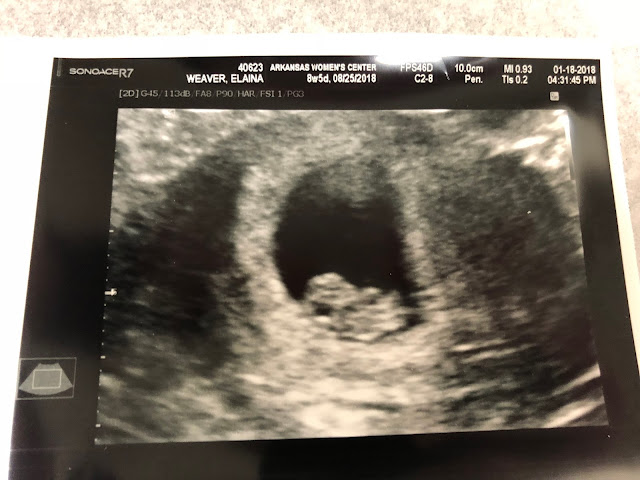

8 Weeks 5 days and our 1st Doctor Appointment

We had our first prenatal appointment with the doctor today.  It was supposed to be Tuesday but my doctor's office was closed for the day due to snow.  I was a little disappointed but I don't think I was nearly as disappointed as some of our family members.

I know without a doubt that if the ultrasound room was big enough we could have easily packed it full of friends and families. I had wanted Andrew to video the appointment, especially the heartbeat so we could share with everyone.  But it all happened so fast.  I think we were both in shock.

By the time I walked into the ultrasound room and she begin looking for Baby I was just in shock at it all I think.  I couldn't speak.  I couldn't even really comprehend all that was going on.  A thousand thoughts were running through my head all at once.

Suddenly we heard the most amazing sound in the world.

Sweet Baby's heartbeat.

180 perfect beats per minute.

She told us Baby measured one day off from what we thought so my doctor probably wouldn't change my due date.

Best Moment This Week: Hearing that heartbeat and getting our first pictures of Baby.